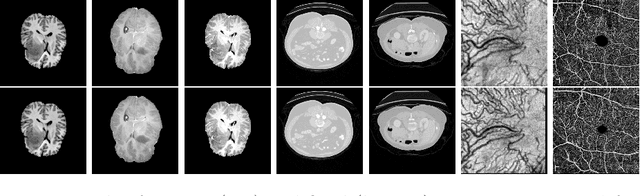

Abstract:Non-rigid registration is a necessary but challenging task in medical imaging studies. Recently, unsupervised registration models have shown good performance, but they often require a large-scale training dataset and long training times. Therefore, in real world application where only dozens to hundreds of image pairs are available, existing models cannot be practically used. To address these limitations, we propose a novel unsupervised registration model which is integrated with a gradient-based meta learning framework. In particular, we train a meta learner which finds an initialization point of parameters by utilizing a variety of existing registration datasets. To quickly adapt to various tasks, the meta learner was updated to get close to the center of parameters which are fine-tuned for each registration task. Thereby, our model can adapt to unseen domain tasks via a short fine-tuning process and perform accurate registration. To verify the superiority of our model, we train the model for various 2D medical image registration tasks such as retinal choroid Optical Coherence Tomography Angiography (OCTA), CT organs, and brain MRI scans and test on registration of retinal OCTA Superficial Capillary Plexus (SCP). In our experiments, the proposed model obtained significantly improved performance in terms of accuracy and training time compared to other registration models.